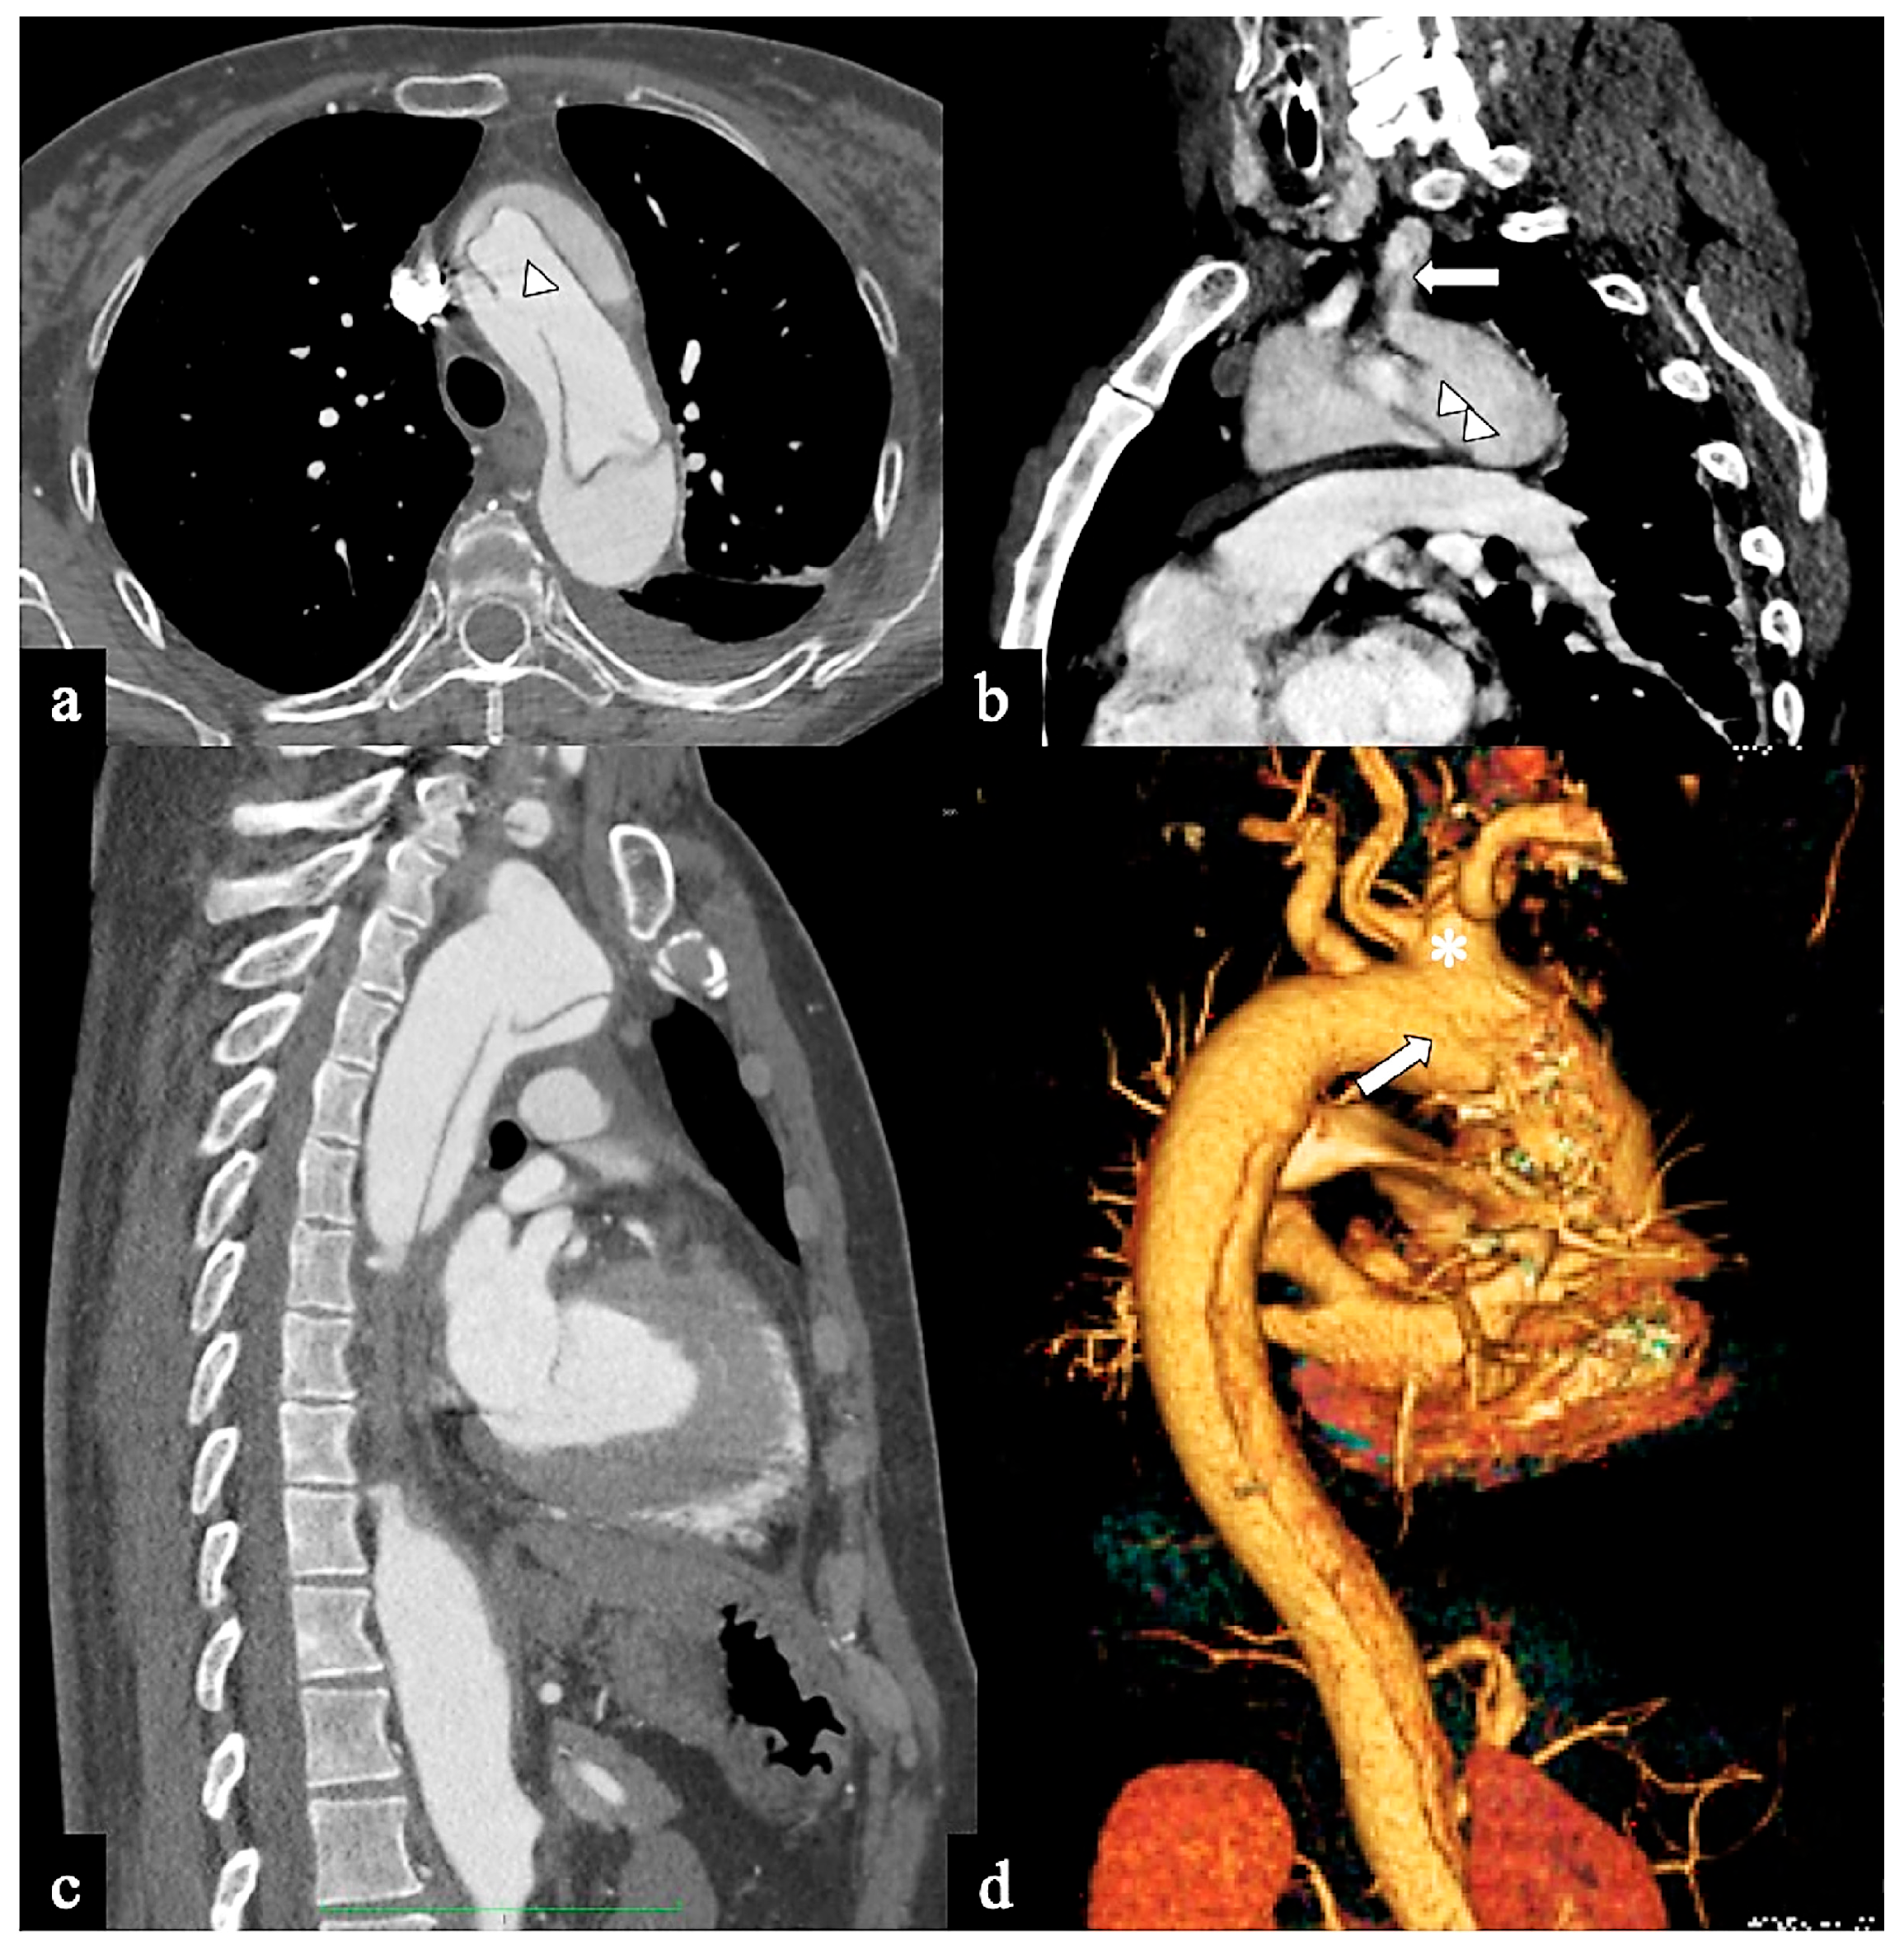

- In Configuration 2, the primary ET is situated within the aortic arch, and the dissection flap is confined solely to the arch (Arch alone). the primary ET is located in the aortic arch and the dissection flap is limited to the arch (Arch alone). This very uncommon configuration occurred in 4 (11%) patients (Figure 4) and is a very rare clinical entity. Configuration 2 is similar to the “group B” definition provided half of a century earlier by Dubost and colleagues [36], reported by Pasic in 1999 [37], and again proposed by Urbanski in 2016 [26]. An amount of 2/4 of these Arch alone patients received continued medical management with close imaging surveillance, and one- and two-year follow-up CTA examinations showed no dissection progression; 2/4 patients underwent hybrid or open surgical repair, one due to persisting pain, and the other one for cerebral malperfusion on follow-up CT.